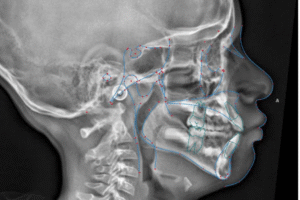

At Bloor West Dental, Health and Wellness, patients are screened for signs and symptoms of sleep disordered breathing (SDB).  If indicated, early interventional orthodontics is recommended at different stages depending on individual patient needs. Functional Appliance This treatment is recommended for patients with signs and symptoms of SDB.  It is conservative and is usually our…

Craniofacial Growth Guidance is proactive and therapeutic approach in dentistry and orthodontics which monitors and steers the development of a child’s jaw, face and airway into proper alignment during the peak growth years.  The treatment intervenes early to address narrow palates, primary crowding, crossbites, receding jaws, breathing issues and signs and symptoms of sleep disordered…